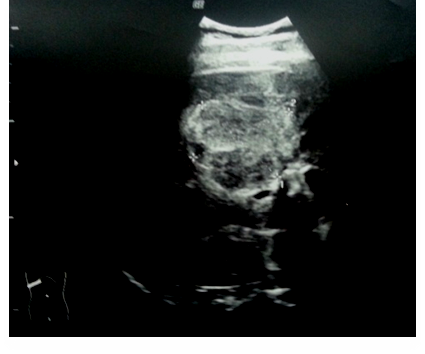

Капиллярные гемангиомы проявлялись в виде множества мелких полостных структур, сливающихся в однородное солидное образование с мелкосетчатым структурным рисунком (15,25 %; n = 9). Форма их округлая или эллипсоидная, контуры четко дифференцировались (кроме случаев выраженных диффузных изменений печени), они обычно располагались вблизи ветвей печеночных и воротной вен, эхоструктура была равномерно однородная, гетерогенная, эхогенность повышена (рис. 2).

Рис. 2. Ультразвуковое изображение капиллярной гемангиомы правой доли печени. Эллипсоидной формы образование повышенной эхогенности с четкими контурами с мелкосетчатым структурным рисунком